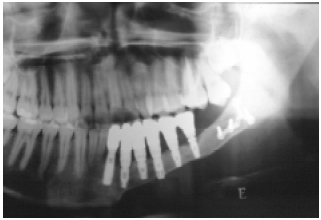

Após a reconstrução óssea da mandíbula, observamos os pacientes por um período de 1 ano a fim de avaliar a integração dos implantes ósseo-integrados pelo segmento ósseo reconstituído. Os implantes foram colocados pela equipe do Serviço de Cirurgia Buco-maxilo-facial da instituição citada anteriormente (Figuras 4 a 8).

Figura 6 - Primeiro tempo da reconstrução com implante ósseo-integrado.

Figura 7 - Segundo tempo da reconstrução com implante ósseo-integrado.

Figura 8 - Resultado da reconstrução com os implantes e a dentição final.

Os pacientes reconstruídos com o retalho de fíbula que evoluíram com sucesso, ao receberem os implantes ósseo-integrados, apresentaram recuperação funcional semelhante aos pacientes reconstruídos com o retalho de crista ilíaca, sendo possível o retorno à mastigação após 6 meses (Figuras 9 a 12).